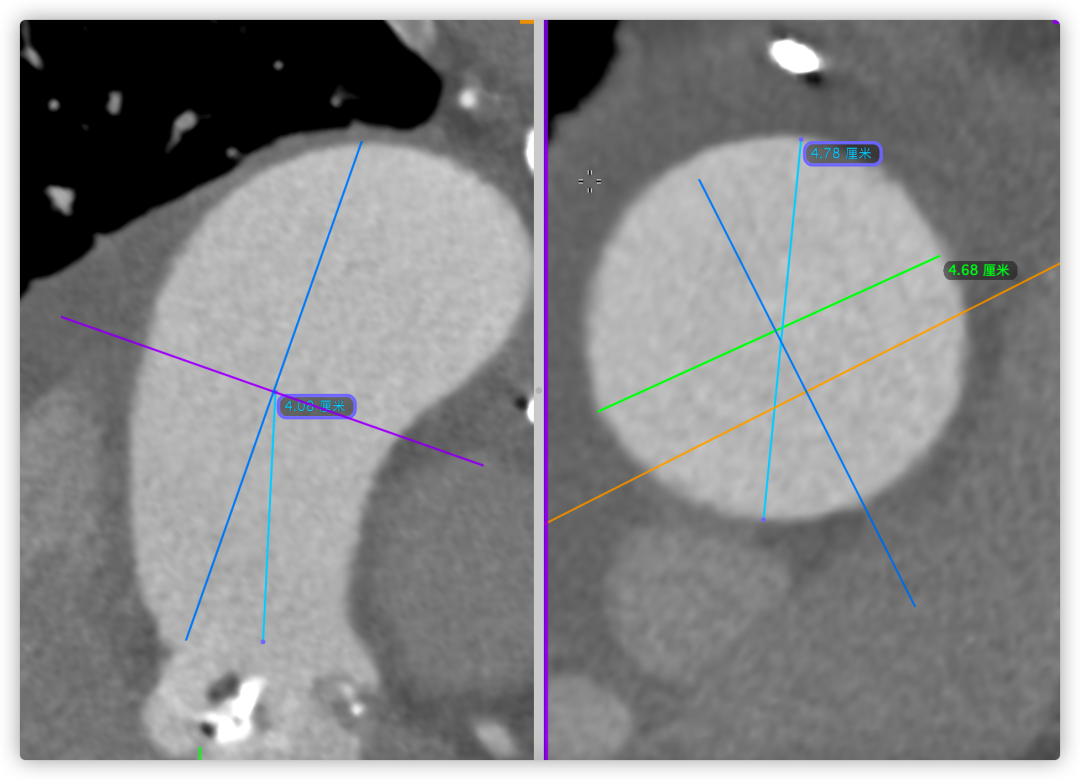

根部角度/瓣环/左室流出道

瓣上结构2,4,6,8,10,12mm

SOV/STJ/AAO